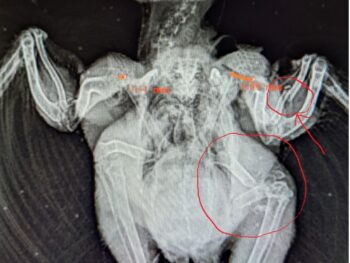

There ARE fates worse than death

My heart cracks a little more every time I see or hear the advice “Don’t take it to the rehabber! They’ll just kill it!” Or Don’t call animal control; they’ll just kill it; or don’t call the game warden, etc, etc. The idea that people who have careers and avocations dedicated to helping animals will […]